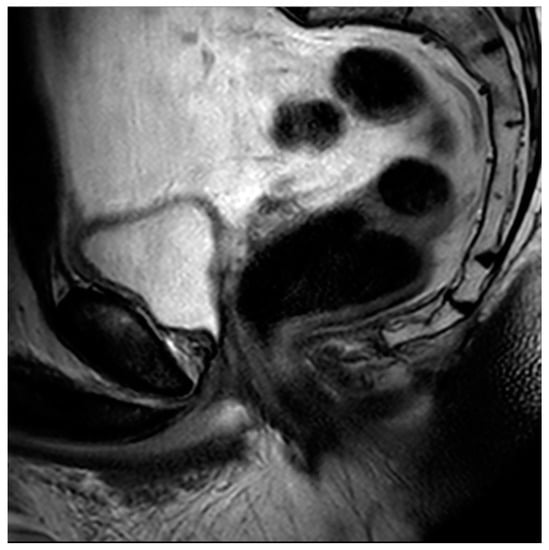

Figure 8. Sagittal T2 image of the pelvis demonstrating a complete absence of the prostate gland with vesicourethral anastomosis following RP.

Radical prostatectomy (RP) is a definitive treatment option for men with prostate cancer in which the prostate and seminal vesicles are surgically removed. The surgical removal of the pelvic lymph nodes may also be offered to men when the chance of nodal metastasis is 2% or higher [81]. Multiple surgical techniques have been described for RP, but the most common approach is robotic-assisted laparoscopic radical prostatectomy (RALP), with up to 90% of all prostatectomies being performed in this manner [82]. Regarding MRI, post-RP changes demonstrate the absence of the prostate gland, with a vesicourethral anastomosis that should have a low T2 signal without early enhancement, nodularity, or restricted diffusion (Figure 8).